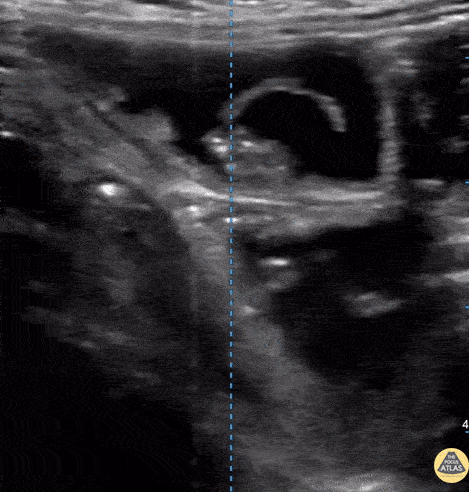

Bowel-GI - Taenia Saginata

Fatigue for the past 3–4 months with mild disturbance of bowel habits. The patient reported visualizing proglottids in the stool. POCUS findings: Ultrasound performed in the left lower quadrant revealed a structure consistent with parasitic segments. Diagnosis: Laboratory confirmation a few days later identified Taenia saginata. Dr. Guillaume Schramme